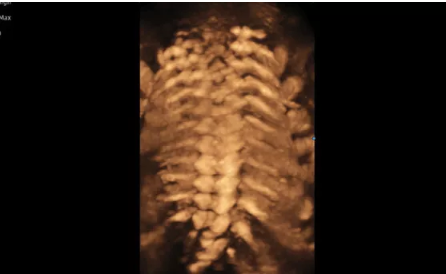

Hera i 10繼承并升級了全球首款5D超聲“三星麥迪遜WS80A”的“晶體結(jié)構(gòu)”成像理念,即將CrystalBeam?波束形成技術(shù)、CrystalLive?超聲成像引擎、S-Vue Transducer?視覺傳感器集于一身,提供更清晰的圖像。

3D/4D成像方面,Hera i 10通過結(jié)合先進(jìn)的圖像渲染技術(shù),著重加強了邊緣和小結(jié)構(gòu)的可視化能力。